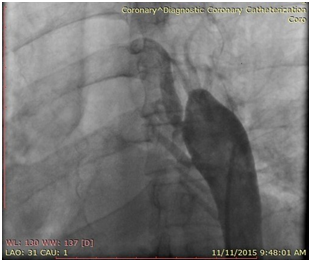

The patient was brought to the endovascular suite and the right groin was prepped. Moderate conscious sedation was administered during the case via a peripheral IV. Access was gained into the right common femoral artery and a 6 French sheath was placed. A pigtail catheter was then placed in the mid descending thoracic aorta and an angiogram was performed demonstrating severe narrowing of the thoracic aorta. The left subclavian artery was not visualized, multiple collateral vessels were seen arising from the mid thoracic aorta. Initial attempts at crossing the stenotic segment with a glide wire and cobra catheter were unsuccessful. The left arm was then prepped and access was gained into the left brachial artery and a 5 Fr sheath was placed. A pigtail catheter was then advanced into the aortic arch and an arch aortogram was performed demonstrating normal branching anatomy with delayed filling of the distal thoracic aorta noted. Simultaneous pressure measurements proximal and distal to the stenosis demonstrated a gradient of 40mmHg. After repeated attempts the stenosis was finally crossed from below using a glide wire and cobra catheter. The glide wire was then exchanged for a 260cm Double Curved Lunderquist wire (Cook Medical). The stenotic segment was predilated with an 8mm by 4cm balloon with resolution of the tight waist seen at 10 atm. The 6 French right groin sheath was then upsized to a 11 Fr sheath. A 20mm diameter by 55mm long Wallstent (Boston Scientific) was then placed across the stenotic segment with the proximal end of the stent positioned just at the origin of the left subclavian artery and the distal end within the descending thoracic aorta past the focal stenotic area. As the stent was unsheathed it migrated distally and opened up distal to the stenotic segment. A 3.9cm long covered balloon expandable Cheatham-platinum (CP) stent (NuMed Inc) was then selected and hand crimped on a 16mm by 6cm long Z-MED (NuMed Inc) balloon. The existing short 11 Fr sheath was replaced for a 70 cm long 11 Fr Mullens sheath which was advanced past the stenotic segment. The balloon mounted stent was then accurately positioned once again, taking care not to cover the left subclavian artery. The sheath was pulled back repeat angiogram performed from the left subclavian artery catheter, and the balloon was carefully inflated. The balloon was deflated and removed. Completion angiogram from the arm approach demonstrated accurate placement of the stent with significant improvement in luminal diameter noted. Repeat simultaneous pressure measurements across the stent demonstrated no residual gradient. The patient was then transferred to the recovery bay were the sheath was removed once the ACT was below 170. The patient had an uneventful post-op recovery and was discharged the following day. At one week clinical follow up, the patient reported significant improvement in symptoms (Figures 1‒4).

Figure 2 Aortogram from the ascending aorta (left brachial approach) demonstrated severe occlusion of the thoracic aorta just pass the origin of the left subclavian artery with multiple thoracic collaterals noted.